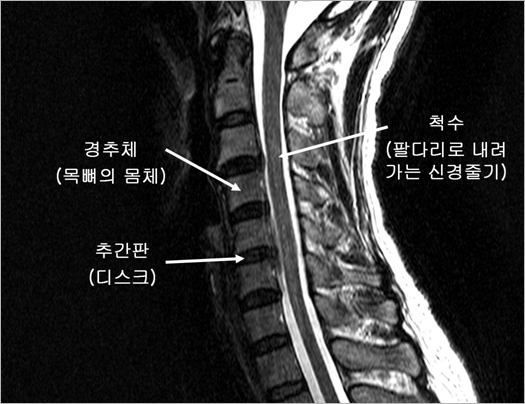

| 경추 인공디스크는 말 그대로 인체내에 정상적으로 존재하는 경추 추간판(디스크)을 모방하여 제작된 인체 삽입용 의료기기입니다. 경추 인공디스크에 대해 이해하시려면 먼저 정상적인 경추(頸椎; 목척추)의 구조부터 간단히 아실 필요가 있습니다. 척추는 두개골부터 골반까지 이어지는 우리 몸의 기둥과 같은 구조물로서 정상 성인에서는 26개의 뼈로 이루어져 있습니다. 이 중 목부위에 있는 경추의 앞부분은 7개의 경추체(頸椎體; 장기알 모양의 척추 몸통 부위)와 각 경추체 사이에 끼어있는 추간판(椎間板; 디스크)으로 이루어져 있습니다(그림 1). |

| • 그림 1 경추의 구조 |